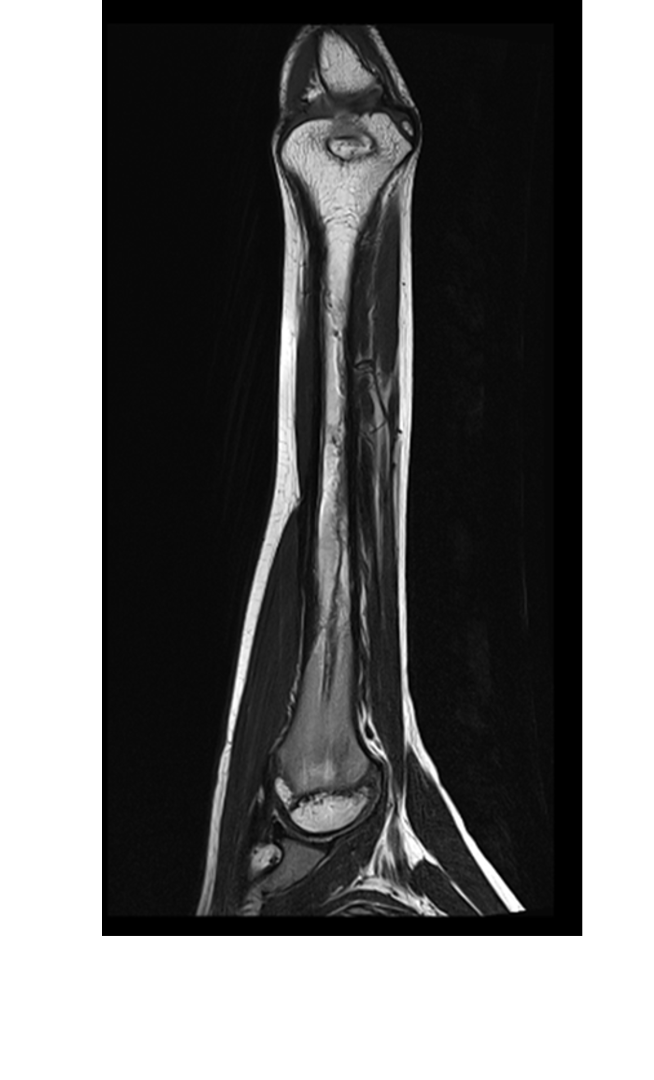

- (A,B) : MR LEFT FOREARM

- B 1 : Tract of previous intramedullary nail seen in shaft of humerus, along with mild diffuse cortical thickening.